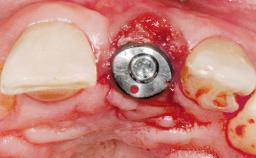

A 42-year-old female patient was referred to our clinic at the School of Dentistry of the University of São Paulo in November 2004, presenting a deficient restoration in the upper left central incisor. The clinical examination revealed no gingival retraction or any signs of gingival inflammation and, therefore, previous periodontal treatment was not considered. The patient presented a high lip line at full smile and a thin tissue biotype. This combination characterized a high-risk situation from an anatomic point of view, which required careful preoperative planning and cautious surgical execution.

Placement Protocol Immediate implant placement

Tooth Site Maxillary incisor or canine

Socket Morphology Single-root socket

Socket Integrity Sufficient, with intact bone walls

Bone Volume Sufficient, with intact walls

Loading Protocol Immediate